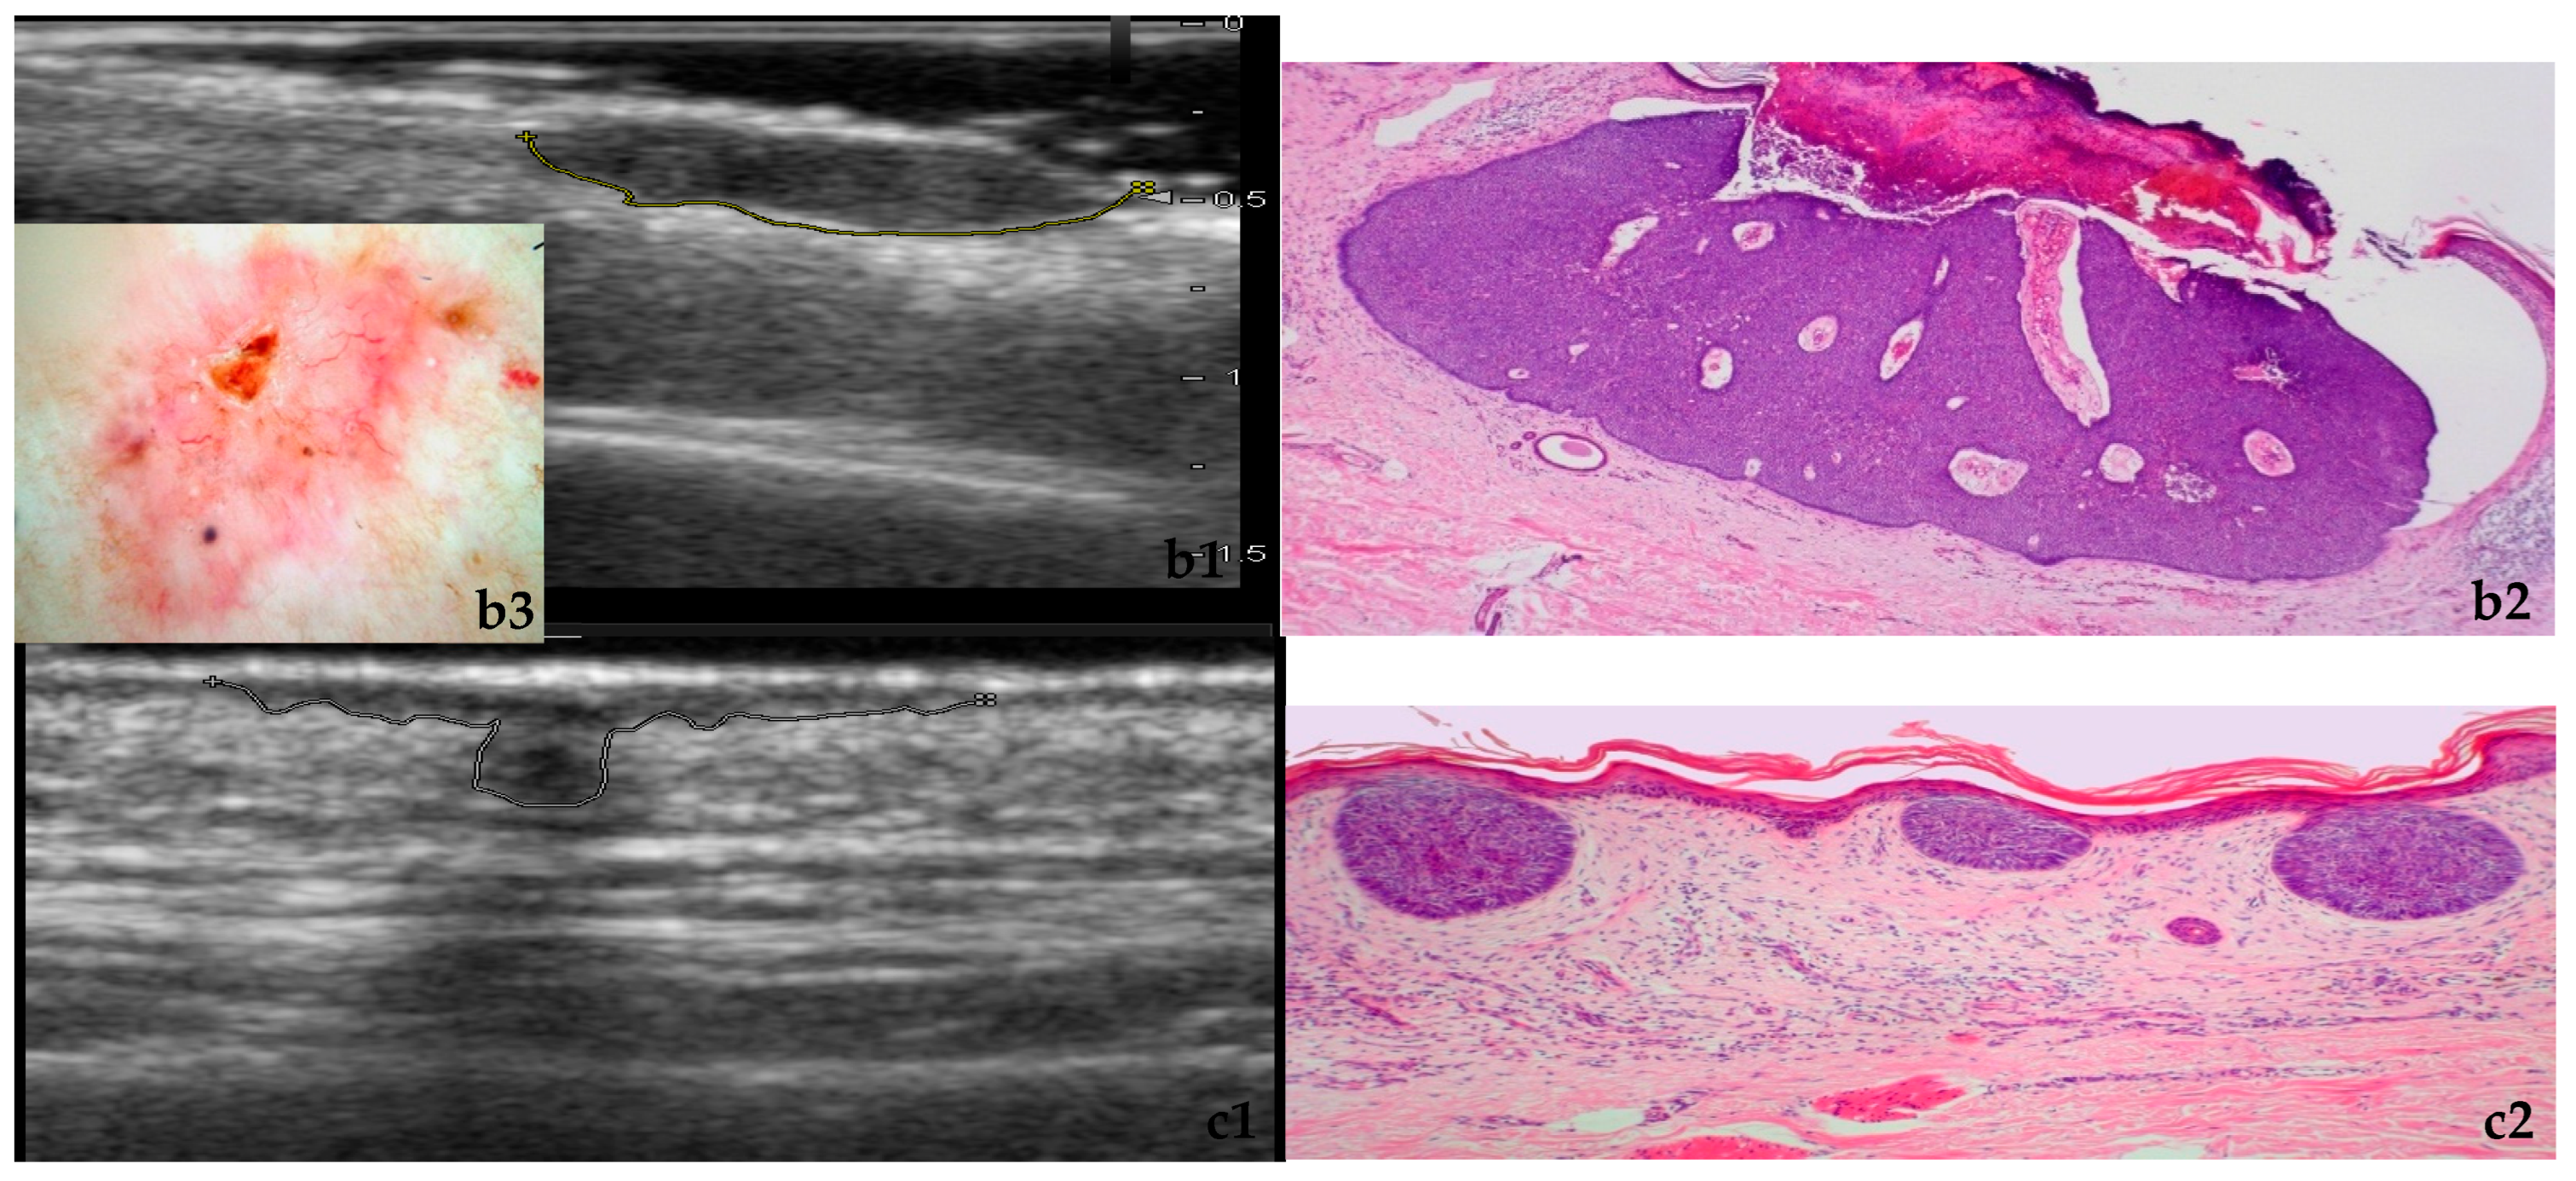

3.1. Morphology and Vascularity

| Feature | Solid Lesions | Infiltrative Lesions | Statistical Association |

|---|---|---|---|

| Contour | Mostly well-defined margins | Mostly irregular/ill-defined margins | OR = 71.9, 95% CI: 37.0–139.8 χ2 = 24.7, df = 1, p < 0.001 |

| Vascularity | More commonly hypervascular | Strongly predisposed to hypovascularity | OR = 6.06, 95% CI: 3.51–10.46 χ2 = 23.8, df = 1, p < 0.001 |